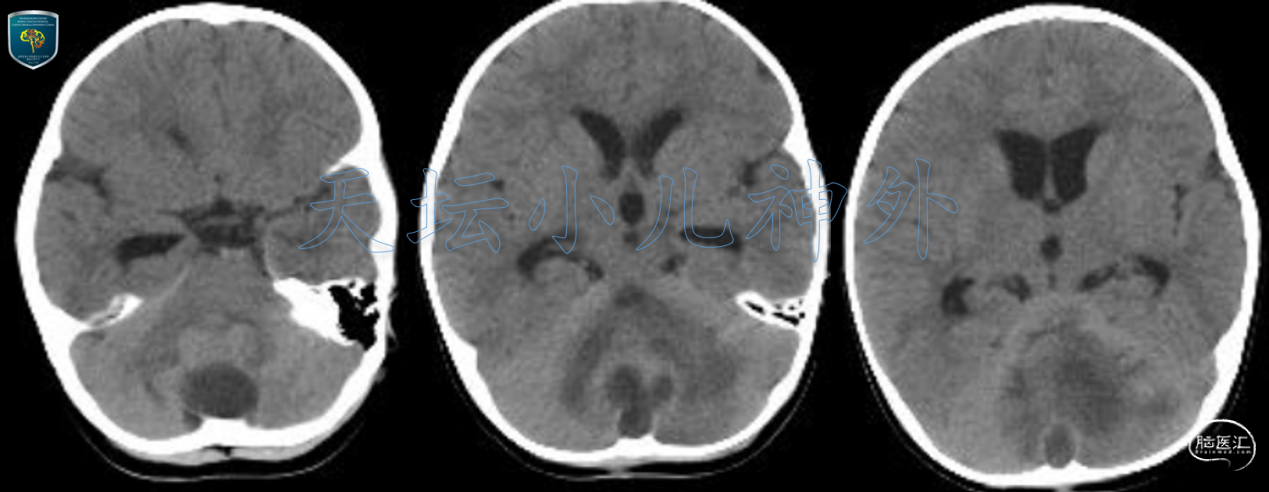

2020年10月接诊一例来自河北省保定市的1岁女性患儿(85cm,11.0kg)。主诉:枕后头皮感染清创术后3月,发现颅内占位一月余。患儿出生时发现枕部头皮小包块、表面生长有硬韧的毛发,未予重视。3月前局部外伤后枕部包块迅速增大,于当地医院行包块切除,术后高热,行头孢噻肟抗菌治疗20余天后好转,复查头部CT发现颅内占位,考虑髓母细胞瘤,遂来我院就诊。门诊查体示:患儿神情,精神状态好,查体欠配合,枕后局部切口愈合好,无红肿及溢脓溢液,余神经系统查体阴性。我院头颅CT显示:后颅窝中线团块状低密度影,边界模糊,密度不均,周围可见大片水肿区,大小约46X45mm(图1);头颅MRI提示后颅窝中线处长T1长T2病变,局部囊性变,囊壁光滑,边界不清晰,DWI呈显著弥散受限,多发囊腔显著环形强化,病变周围水肿明显,脑脓肿可能性大(图2)。

图1. 后颅窝中线团块状低密度影,边界模糊,密度不均,周围可见大片水肿区,大小约46X45mm。